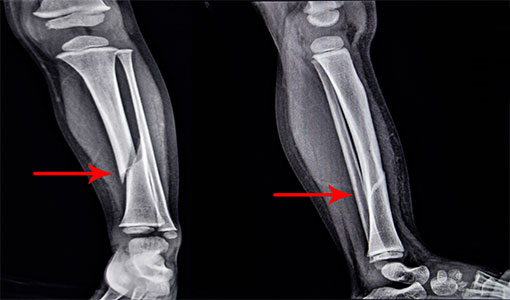

Not that long ago, my mother discovered she had severe bone loss. It was like a dagger to her heart, because she was always so active. She resented feeling “shut in” by bone loss, out of fear that one wrong move could cause a fracture.

But her DEXA scans weren’t improving.

If it could happen to my mom, it could happen to anyone. And I knew I wouldn’t be far behind…